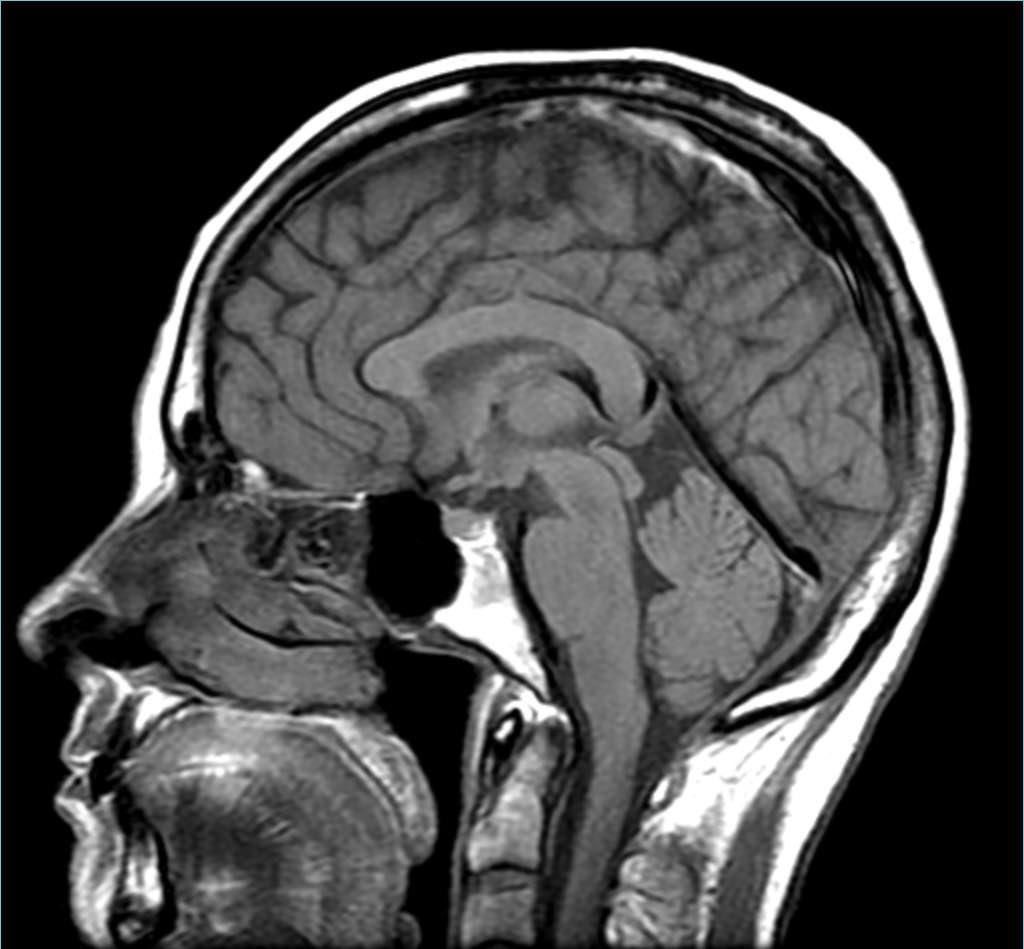

Ø 功能性磁共振成像(Functional Magnetic Resonance Imaging,FMRI)

• 规模:大(能够显示整个大脑的信息)

• 分辨率:空间分辨率为中低,时间分辨率为极低

• 侵入性:非侵入性

FMRI 不是传统的脑机接口工具,但它是一种典型的记录工具——它能告诉你大脑内部的情况。

FMRI 能够扫描整个大脑,生成三维模型。

FMRI 的主要缺点在于分辨率,它扫描生成的图像确实会有一个分辨率,正如电脑屏幕上会有像素一样,只不过它的像素是三维立体的——也就是所谓的「体素」(voxel);

其次是在于时间分辨率。FMRI 所追踪的血流量并不精确,而且会有大约一秒钟的延迟。